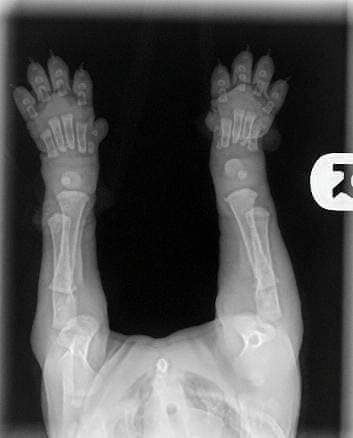

Lorsque vous obtenez vos chiots âgés de 8/12 semaines, veuillez garder cette image à l'esprit!!

Leurs os ne se touchent même pas encore. Ils marchent si gentiment avec de grosses pattes souples et un mouvement bancal parce que leurs articulations sont entièrement constituées de muscles, de tendons, de ligaments recouverts de peau. Rien ne s'emboîte étroitement ou n'a encore de véritable prise.